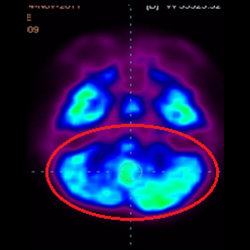

干細胞治療腦癱后改善的客觀放射學證據

細胞治療后,藍色和黑色區域減少,并且看到更活躍的區域。這表明損傷減少并改善了大腦功能。

細胞治療前 PET CT 掃描顯示神經組織中的藍/黑色區域,表明腦癱引起的大腦損傷。

這證明細胞療法是治療腦癱兒童安全有效的方法。細胞療法可以更新大腦損傷的核心,并且可以通過 PET CT 掃描來監測大腦的改善情況。這些細胞療法與標準治療一起促進腦癱兒童的生長和改善。